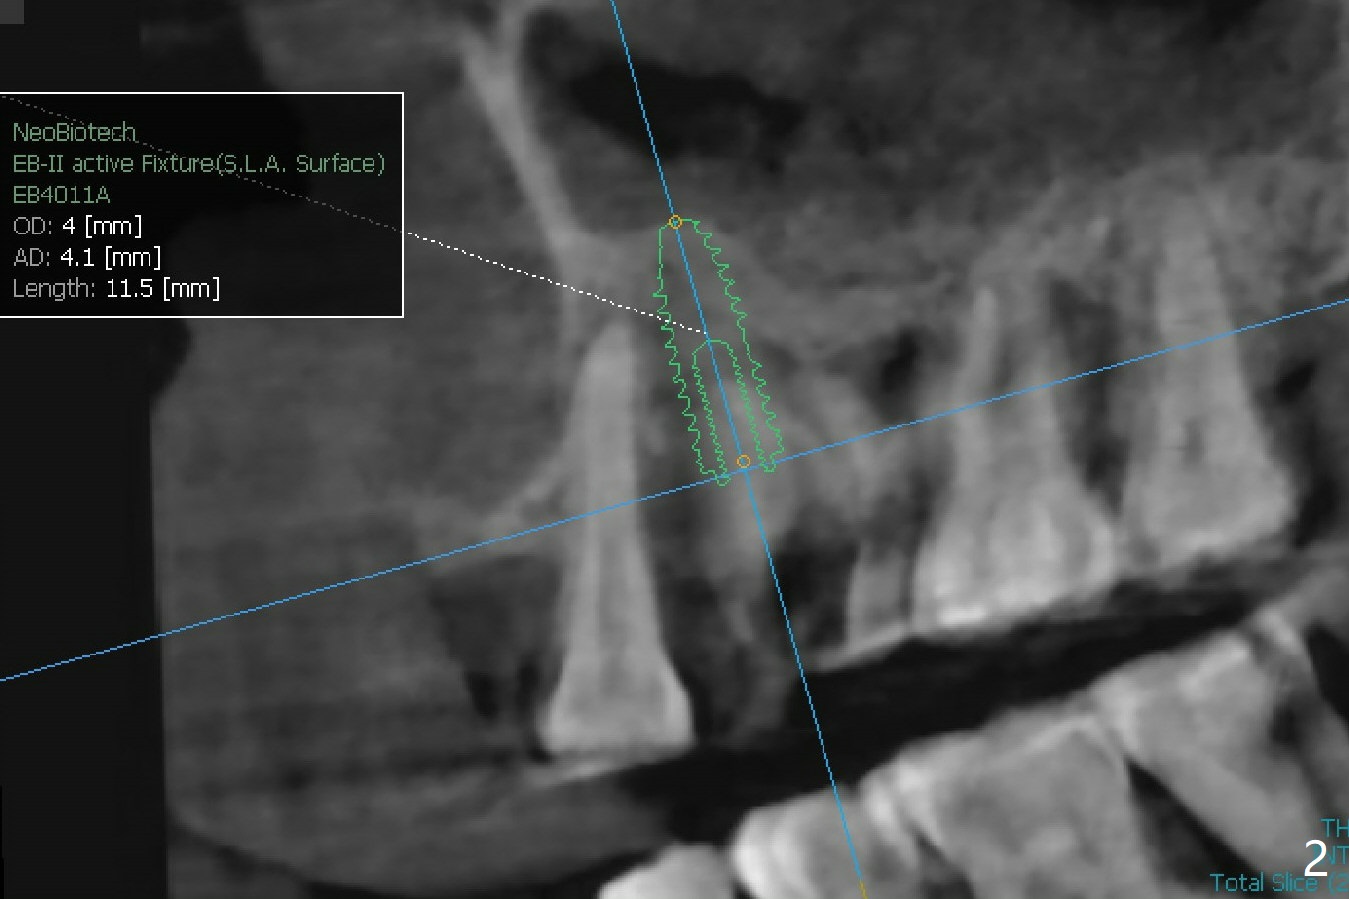

There is more bone apical to the residual root at #13 (Fig.1 red line). An immediate implant along the long axis of the root can be longer, 11.5 mm, favorable for primary stability (Fig.2 (CT taken immediately preop)). The initial trajectory is not ideal (Fig.3). When the pointed/Lindamann bur is removed (Fig.4), effort is made to move the apical end of the osteotomy distal (Fig.5 red arrow) by removing the apical bone (red dashed line). Following sequential osteotomy, a 4x10 mm dummy implant is placed with the trajectory remaining not so ideal (Fig.6,7). As the dummy implant is removed (Fig.8), a new osteotomy is established distal to the existing one (Fig.9). Subsequent drills gradually shift into the original osteotomy (Fig.10 red arrow). When the same dimension dummy implant returns, the trajectory improves with decreased stability (Fig.11). It seems reasonable to place a larger implant without further osteotomy. After placing PRF membrane and Vanilla graft for sinus lift (Fig.13 *), a 4.5x10 mm definitive implant is placed with loss of control in the trajectory (Fig.12,13).